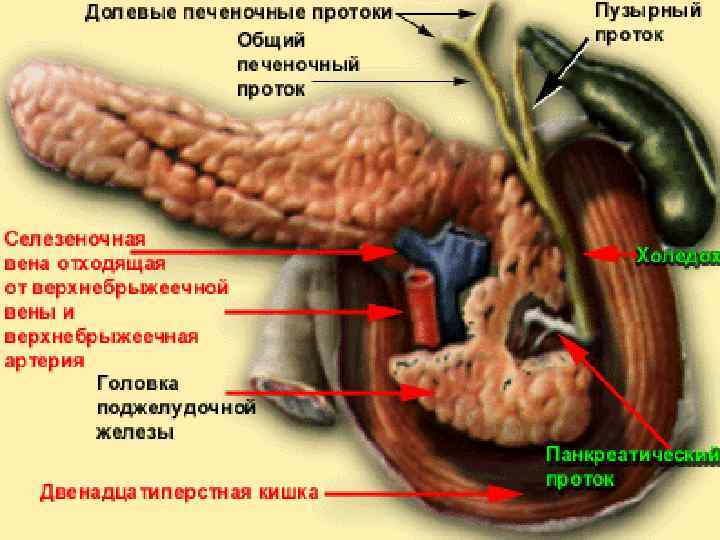

Анатомия и особенности Гартманова кармана желчного пузыря